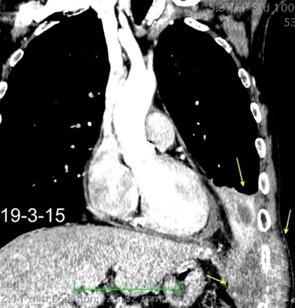

63. HEMOTÓRAX. ANEURISMA ASI ROTO.